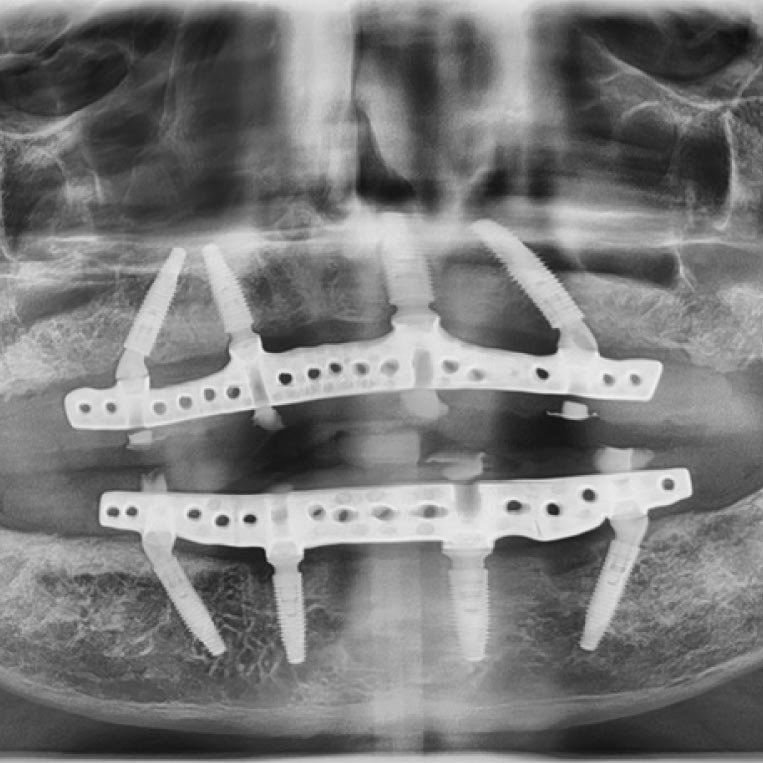

Funcionan como una estructura fija que se atornilla sobre varios implantes previamente colocados en el hueso maxilar o mandibular. La base metálica de la prótesis se une con una parte acrílica que simula encía y dientes. Este sistema combina la estabilidad de los implantes con una prótesis de mayor cobertura, lo que permite restaurar arcadas completas de forma permanente y con una distribución equilibrada de fuerzas al masticar.